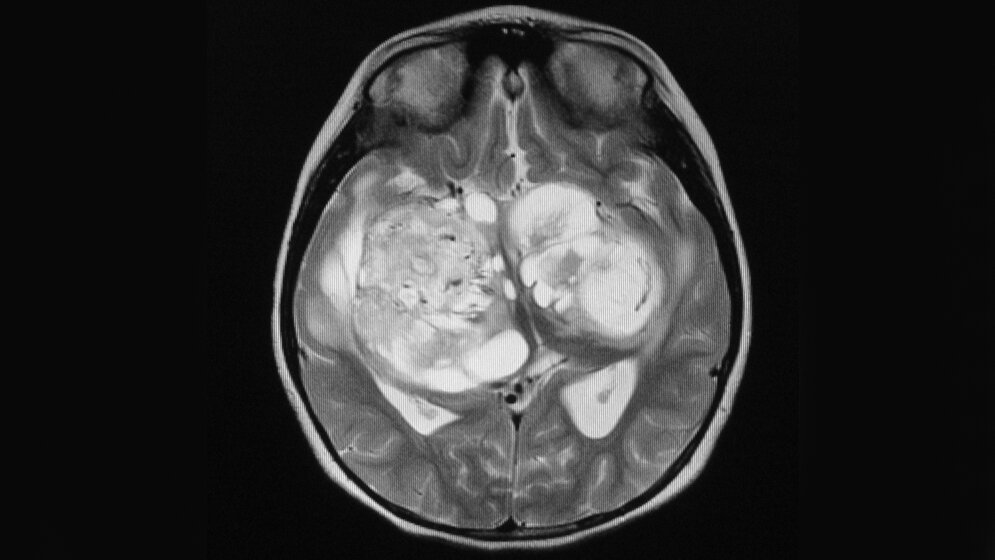

PRG3 heißt das Gen, das vor allem in jungen Jahren im Hirn aktiv ist und das dessen Entwicklung und damit das menschliche Lernvermögen maßgeblich beeinflusst. Das Gen steuert aber auch das Wachstum bösartiger Hirntumoren. Das haben jetzt Wissenschaftler der Friedrich-Alexander-Universität Erlangen-Nürnberg (FAU) um den Neuroonkologen PD Dr. Nicolai Savaskan herausgefunden.

Die Neurowissenschaftler der FAU konnten nun nachweisen, dass dieses Gen in bösartigen Hirntumoren, so genannten Gliomen, häufig entweder im Übermaß oder gar nicht wirkt. Brachten die Forscher die PRG3-Aktivität wieder auf Normalmaß, konnten sie auch das für Gliome typische, schnelle Umsichgreifen verlangsamen und deren Bösartigkeit verringern.